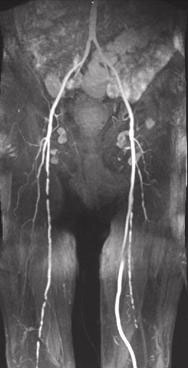

Smoking clogs the arteries and causes heart attacks and strokes - Ukraine

Copyright

Rights to this image are owned by the European Union. To receive information on conditions for use, requests should be addressed to: